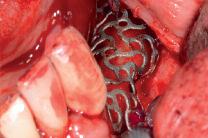

Nach crestaler Schnittführung, vestibulärer und lingualer Abpräparation, vestibulärer Entlastung und Freipräparation des N men talis erfolgte die Periostschlitzung vestibulär

5 | Konditionierung des zu augmentierenden Bereiches mit einem Knochenschaber und kortikalen Bohrungen; Anprobe des passgenauen Gitters

Der gewonnene autologe Knochen wurde mit Geistlich Bio Oss® und PRF gemischt, das Gitter damit aufgefüllt und eingesetzt

7 | Fixierung des aufgefüllten Gitters mit Osteosyntheseschrauben 8 | Ansicht des eingesetzten Yxoss CBR® Gitters 9 | Abdeckung des Gitters mit der GBR Membran Geistlich Bio Gide®